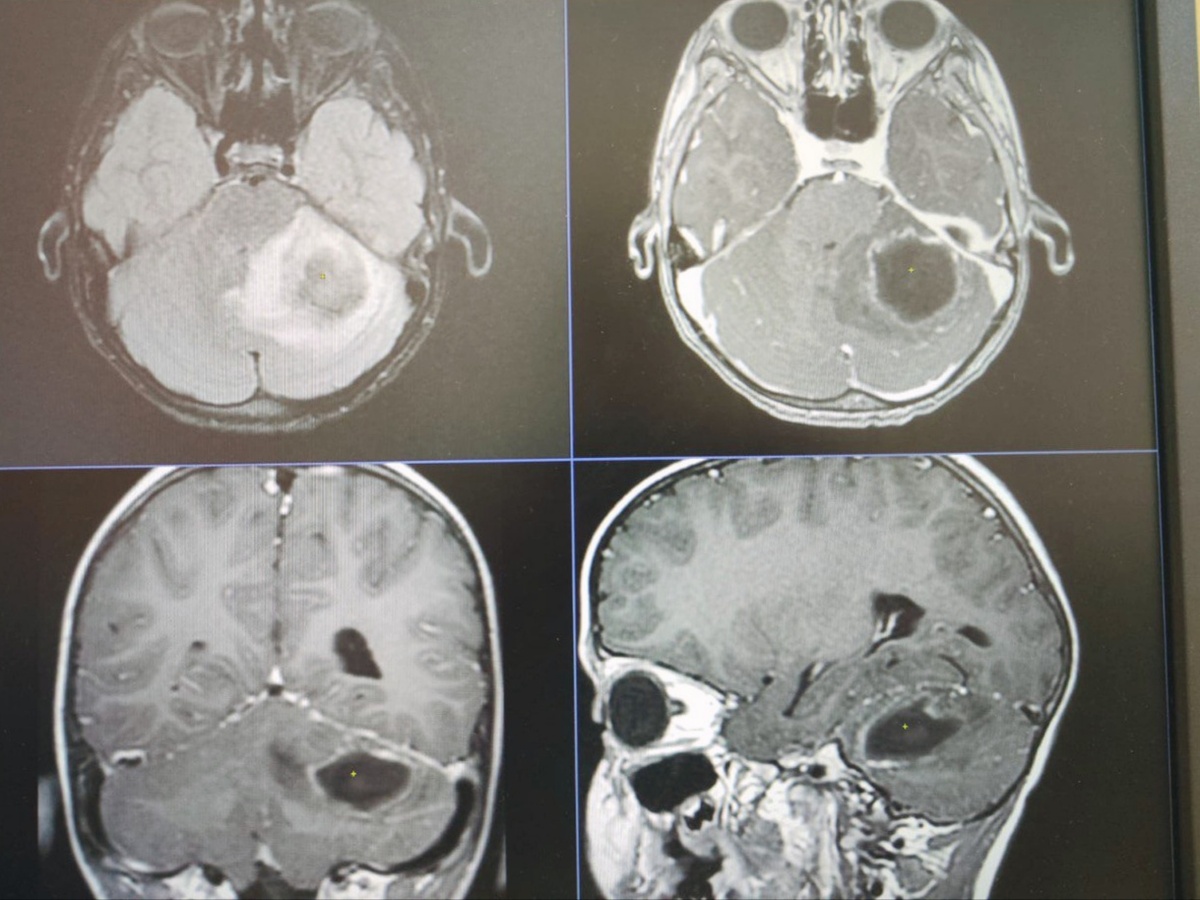

– В экстренное приемное отделение 7 марта поступил мальчик восьми лет с жалобами на рвоту, боль в животе, слабость, вялость, температуру. Хирурги исключили патологию по своему профилю. Но так как симптомы не проходили, было принято решение сделать МРТ головного мозга. Во время исследования у пациента был обнаружен абсцесс мозжечка, что встречается в практике врачей достаточно редко. Нашим коллегой-нейрохирургом Эдуардом Федоровичем Сырчиным была проведена первая часть операции – вскрытие абсцесса. Далее в операционную были приглашены мы. С первого взгляда было понятно, что это пациент именно по нашему профилю – в ухе виднелся гной и был характерный запах, – рассказала врач-оториноларинголог Детской областной больницы Надежда Стрижова.

У пациента был диагностирован отит, он проходил лечение по месту жительства, но заболевание прогрессировало. В итоге из-за скопившегося гноя произошел абсцесс, который и потребовал хирургического вмешательства. Вторым этапом мальчику была проведена операция, во время которой хирург делает разрез за ушной раковиной, вскрывает сосцевидный отросток и позволяет гною вытекать наружу. Во время оперативного вмешательства устанавливается дренаж с целью дальнейшего промывания полости. После этого юный пациент находился в больнице, где ему проводилось дальнейшее лечение. С улучшением он через месяц был выписан домой.